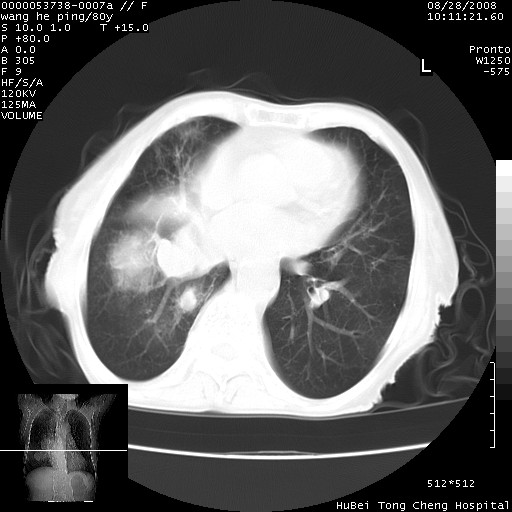

以下是引用黑白光影在2008-8-28 22:33:00的发言:[br]右肺中央型肺癌伴阻塞性肺炎,肺癌肺转移。

以下是引用lshx在2008-8-28 22:06:00的发言:[br]1.右肺中心型肺癌伴阻塞性肺炎,不除外双 肺早期转移。[br]2.心包积液。

以下是引用随光逐影在2008-8-29 7:40:00的发言:[br]1)右肺中心型肺癌伴阻塞性肺炎,肺内转移。2)心包积液(少量)。

以下是引用wqs571018在2008-8-28 21:56:00的发言:[br]右肺中心型肺癌伴阻塞性肺炎可能。

以下是引用liuyue在2008-8-28 22:46:00的发言:[br]1.右肺中心型肺癌伴阻塞性肺炎。[br]2.心包积液(少量)。